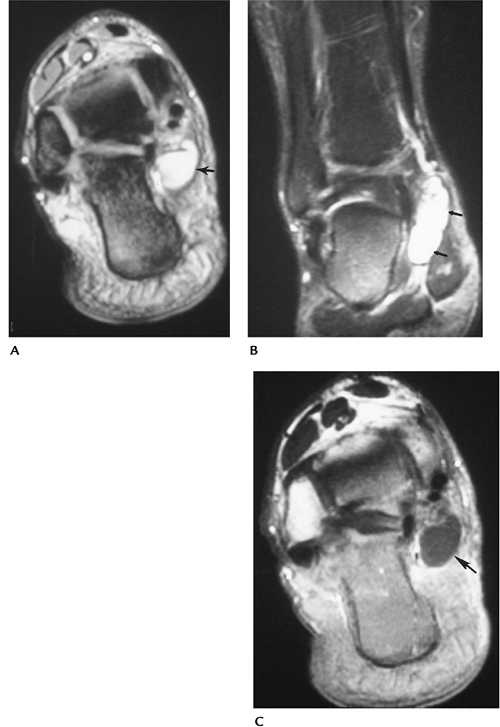

P.733

![]() |

|

FIGURE 10-54 Ganglion cyst. Axial (A) and coronal (B) T2-weighted images showing a well-defined high signal intensity lesion (arrows). (C) Post-contrast T1-weighted image showing cyst wall enhancement (arrow).

Suggested Reading

Feldman F, Surgson SD, Staron RB. Magnetic resonance imaging of para-articular and ectopic ganglia. Skel Radiol 1989;18:353–358.